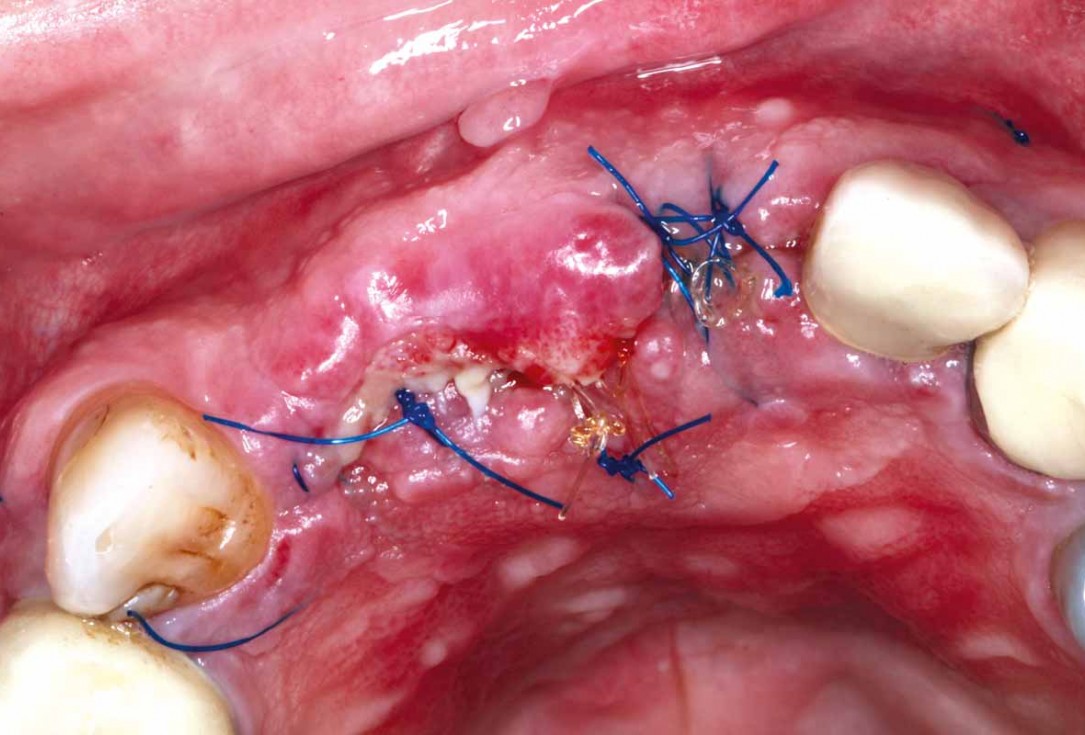

12/27 - Closure without tension using sling sutures

GBR and soft tissue augmentation with cerabone® and mucoderm® - H. Maghaireh & V. Ivancheva

13/27 - Site closed free of tension